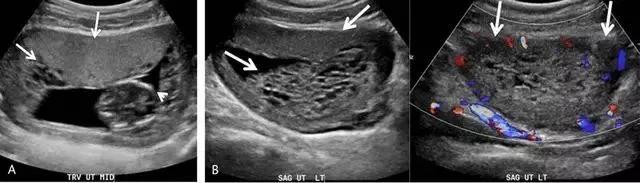

前置胎盘指胎盘覆盖于宫颈内口或位于宫颈内口 2 cm 之内,是晚孕时无痛性阴道出血的重要原因。既往,曾根据胎盘距离宫内口的远近分级为完全性、部分性、边缘性和低置胎盘(图 10)。

2012 年美国妇产科协会对前置胎盘的分类进行了修订,认为边缘性与部分性前置胎盘难以区分,建议只在描述胎盘边缘相对于宫内口的位置。

图 10 示前置胎盘:A 为各种前置胎盘示意图,分别为低置、边缘性、部分性和完全性。B 为孕 20 周的完全性前置胎盘纵切面,箭头示胎盘完全覆盖于宫内口。C 为另一例孕 33 周胎儿的矢状位 T2WI ,星号指胎盘完全覆盖于宫内口。D 为孕 12 周时的低置胎盘矢状面,长箭头示胎盘下缘,短箭头示宫内口,二者距离< 2 cm